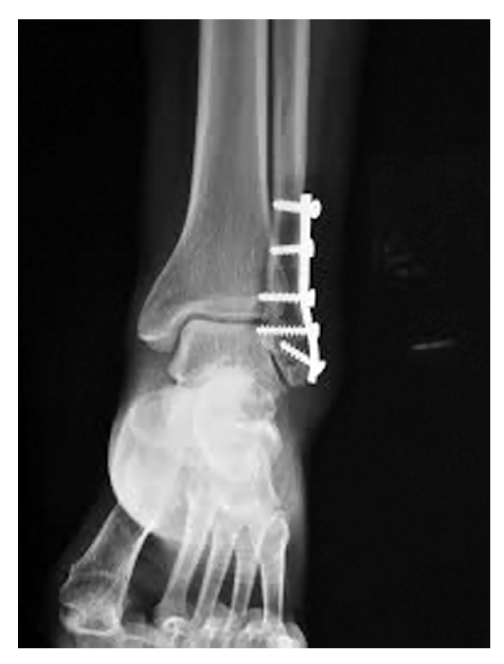

При проведении медицинских судебных экспертиз правильности оказания хирургической медицинской помощи отмечены случаи, требующие оценки возникновения очага остеопороза в области перелома после проведения операции остеосинтеза при переломе нижней трети диафиза малоберцовой кости, чаще при переломе Дюпюитрена (рис. 1).

Рис. 1. Рентгенограмма нижней трети малоберцовой кости с развившимся очаговым остеопорозом в области перелома после операции остеосинтеза металлической пластиной